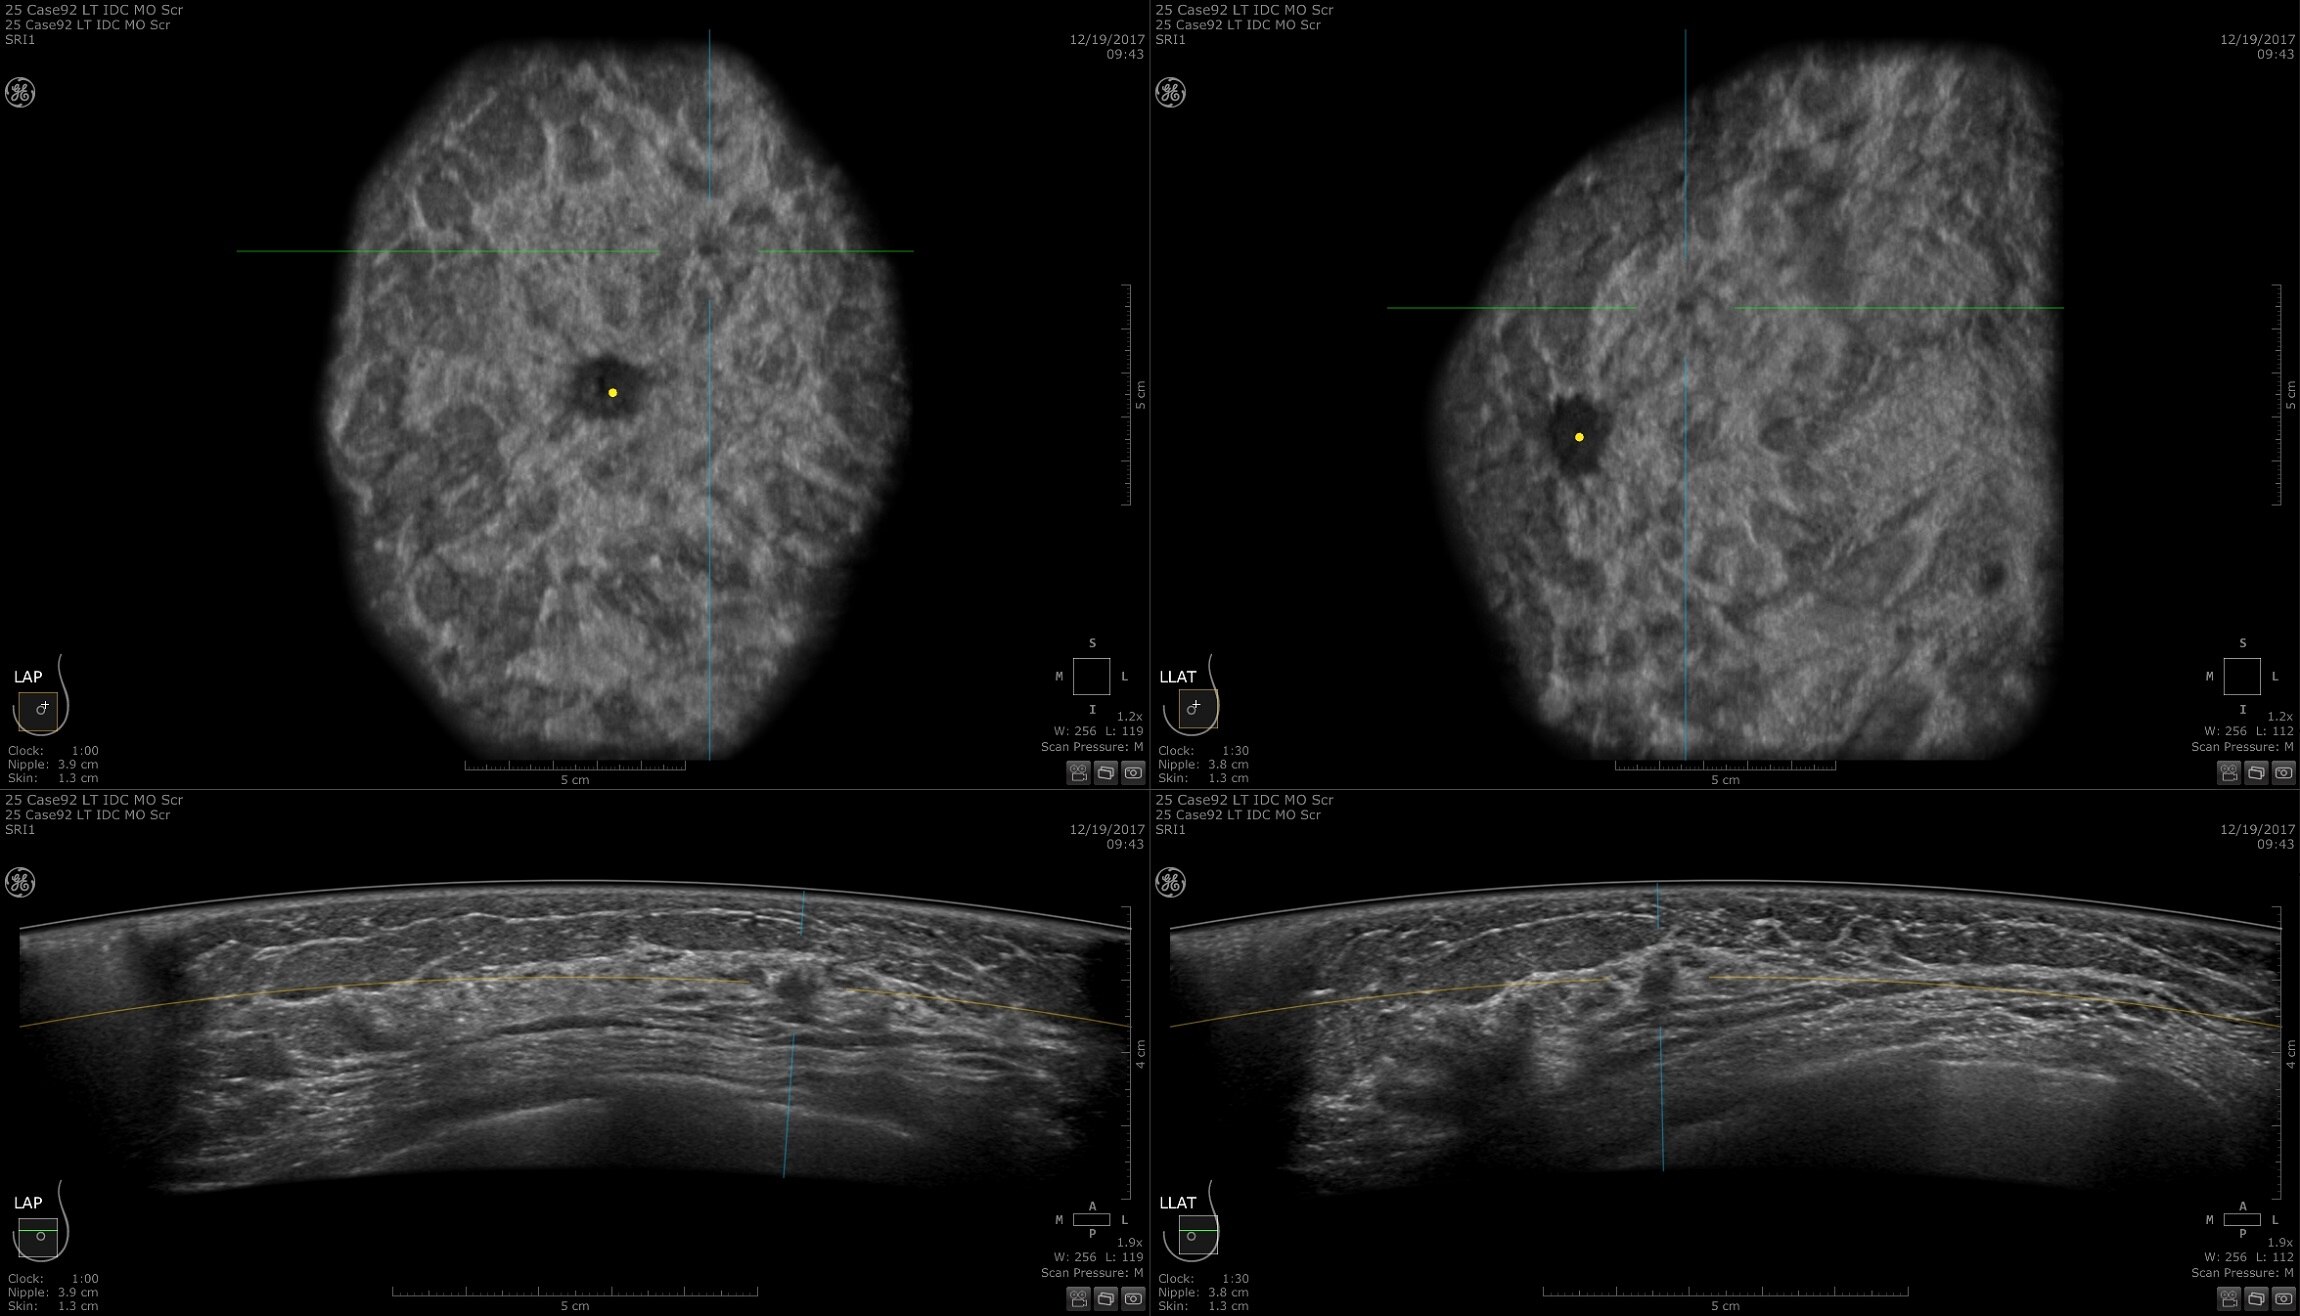

How do you make our best ultrasound even better? Build a more powerful engine with the most progressive and adaptive capabilities yet. Our Lyric Architecture allows for more data — leading to higher spatial and contrast resolution and color sensitivity. It works in harmony with our specialized probe technology to extract more information at record speeds for faster, sharper, and clearer images.

Future proof your practice with the freedom to continuously unlock new imaging and processing power to achieve high resolution, detailed images - even in difficult scanning conditions. Generations ahead, the adaptive nature of Lyric Architecture allows for new imaging standards for years to come.

To uncover answers, you need details. The Voluson Expert 22 elevates 2D imaging with exceptional spatial and contrast resolution for border distinction and tissue differentiation. Utilize Radiant for more definition, UltraHD to see super fine details, and Augment to boost penetration – discovering the answers you seek.